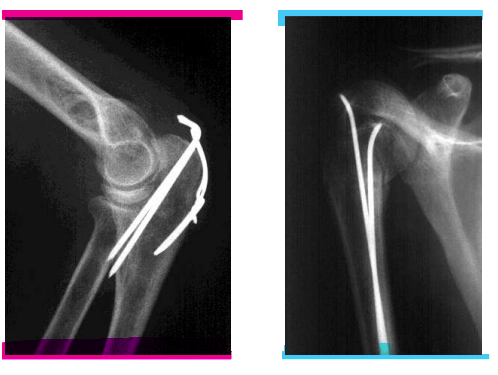

Operative Frakturbehandlung

Kirschnerdraht-Osteosynthese

kleines Loch

manipulation zur besseren einrichtung

erneutes bohren möglich

Zuggurtung - Intramedulläre Schienung

Drähte wandern auch gerne mal aus

nicht so stabil